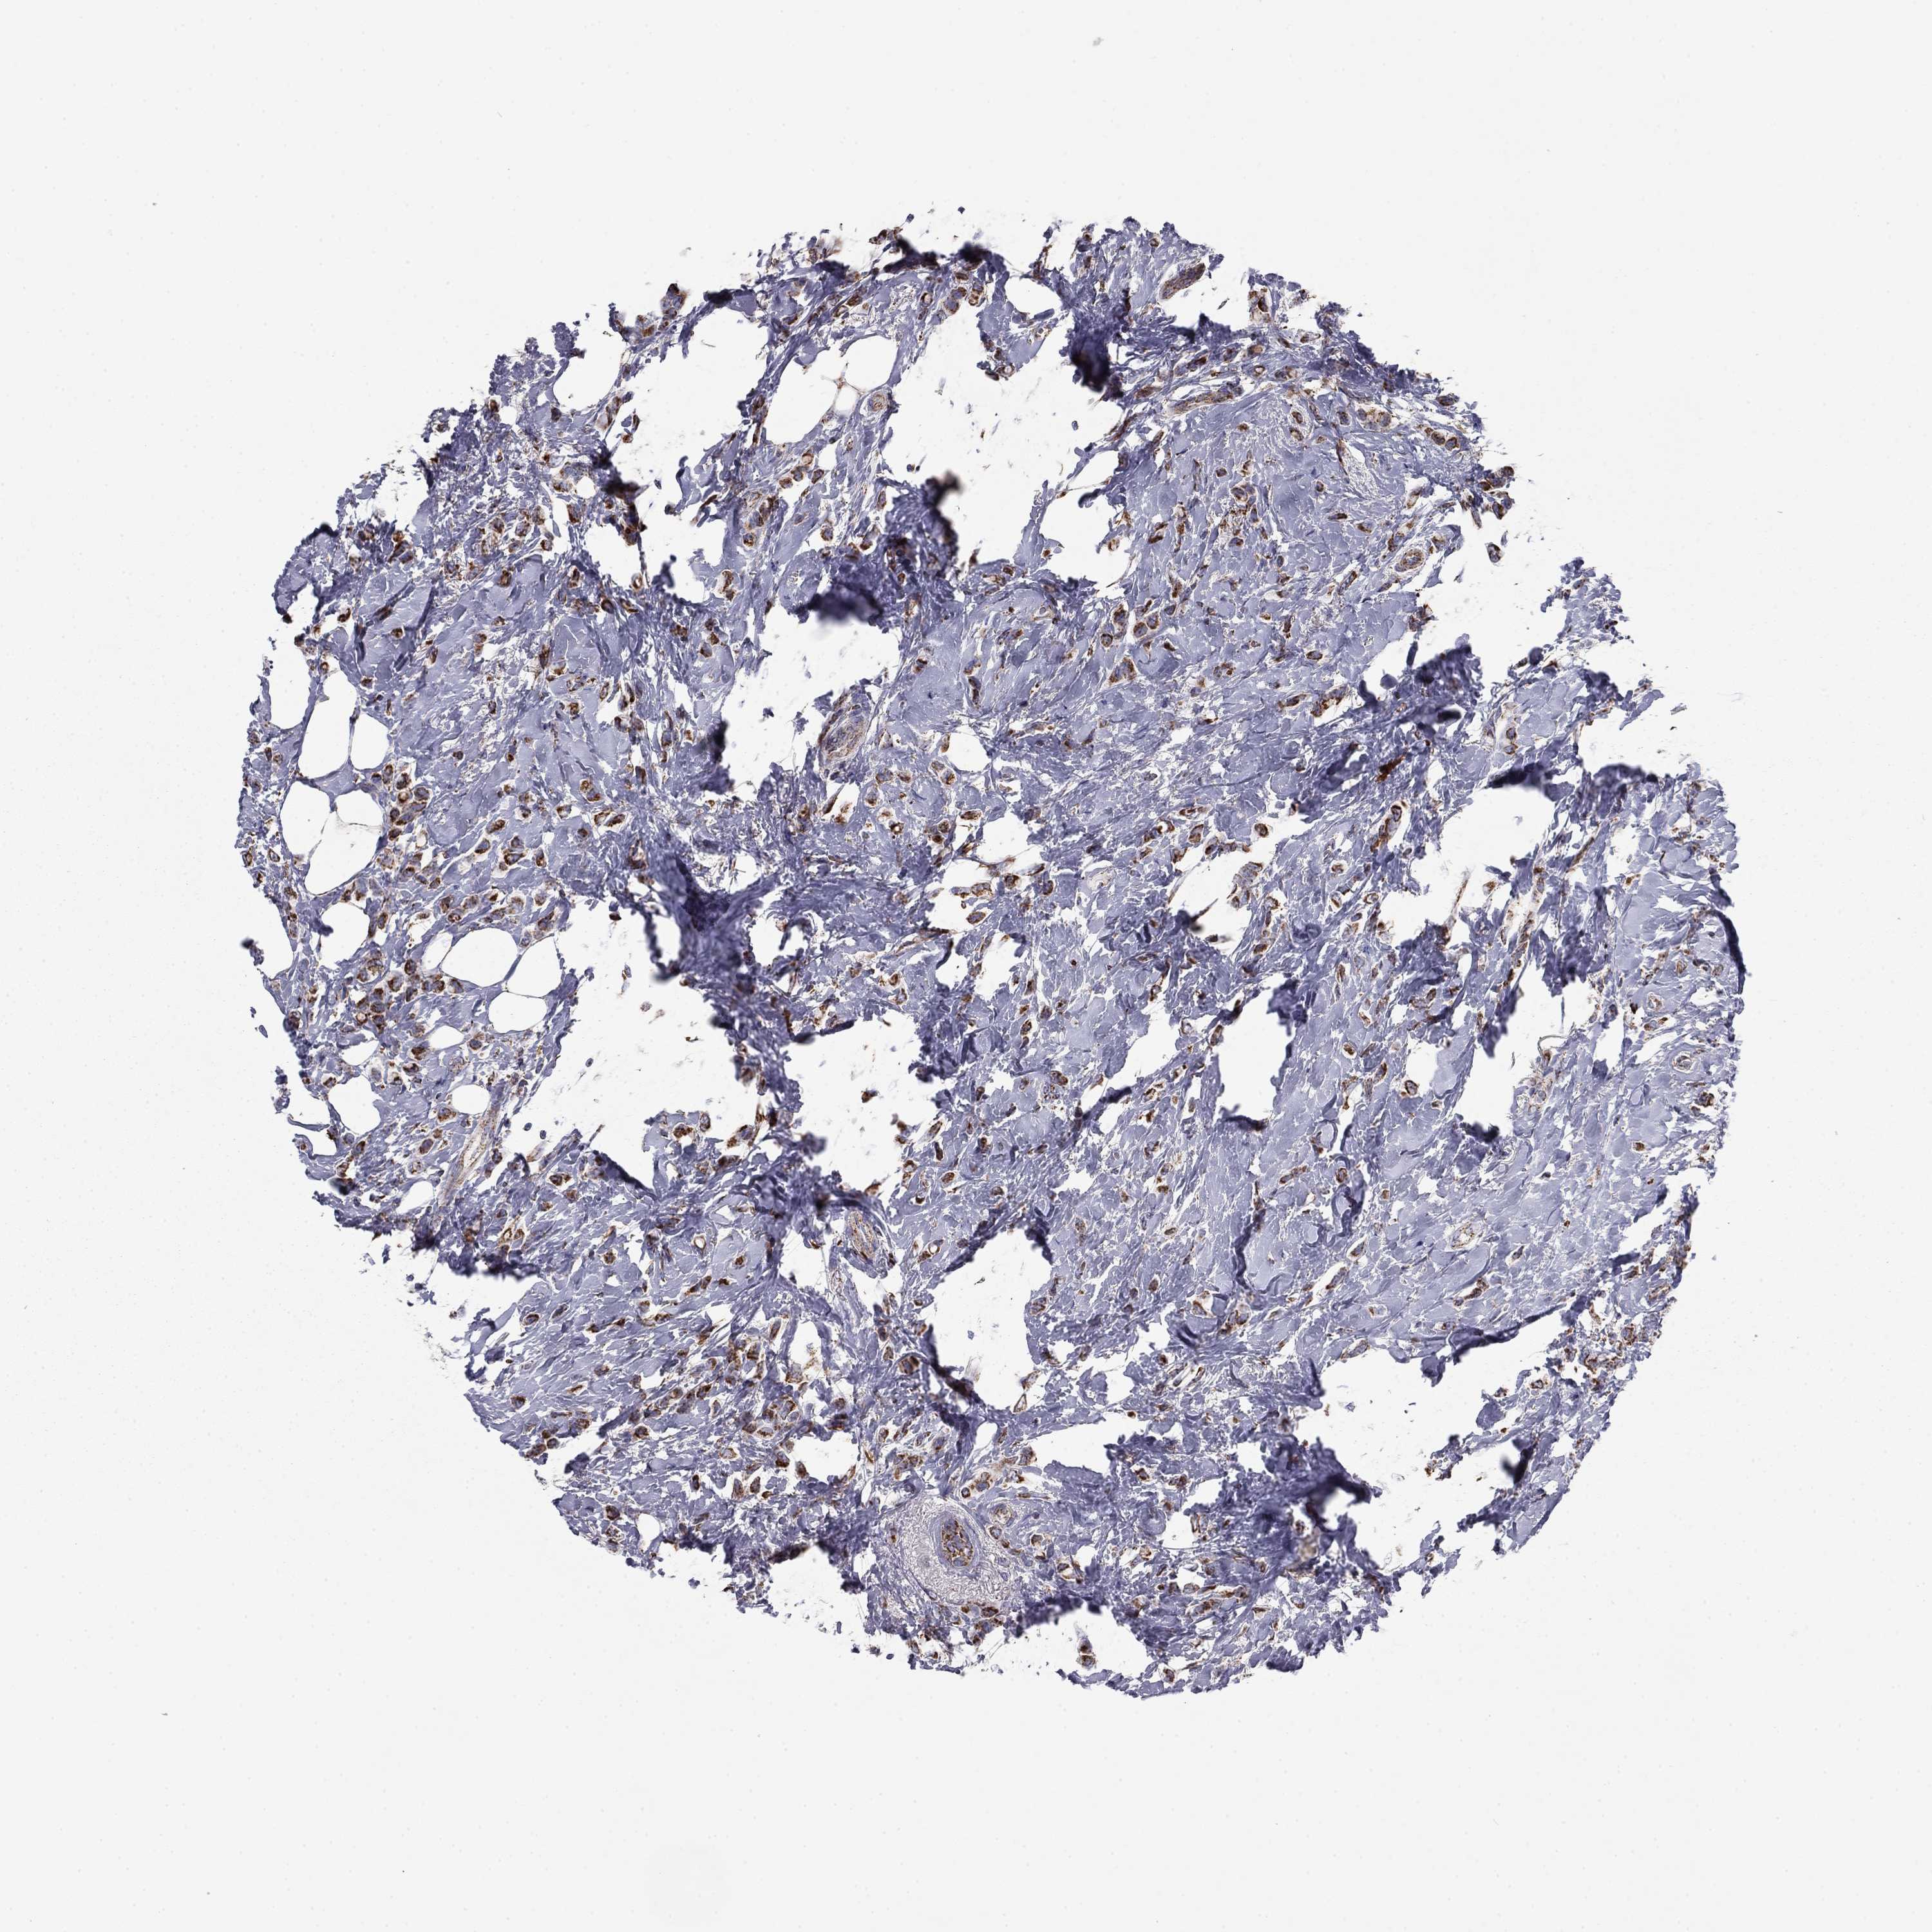

CANCER BREAST CANCER Show tissue menu

Breast cancer

Human cancer